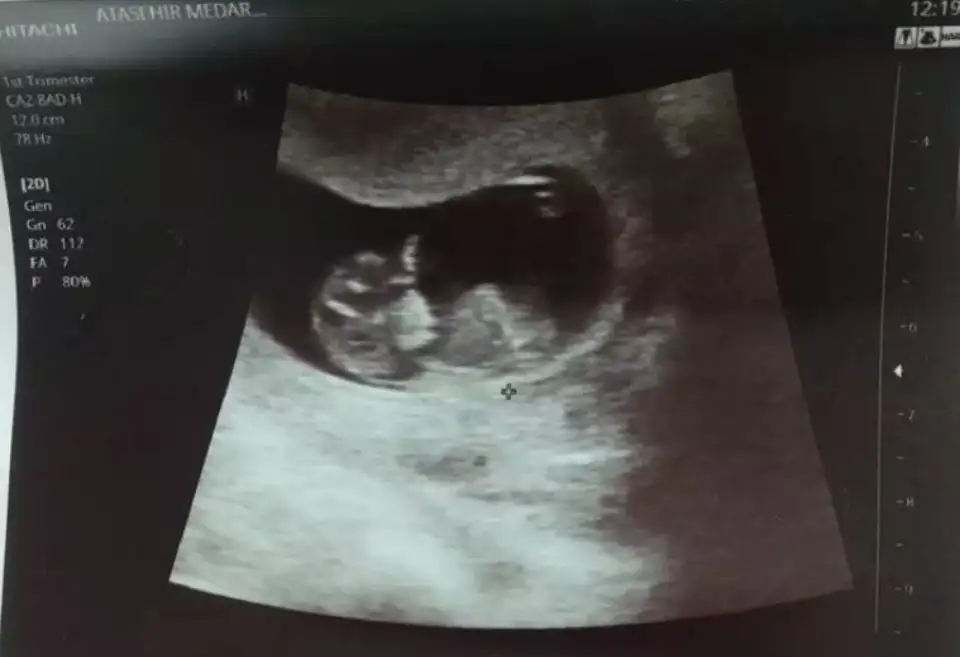

ıkra meyraMerhaba ben bu siteyi yeni keşfettim hamileyim çok şükür benim bebiş 12 haftalık cinsiyetini merak ediyorum doktor birsey demedi. Bana kız gibi geldi ama bilemedim Size foto gönderiyirum tahmin eder misiniz

Kız görünüyorMerhaba ben bu siteyi yeni keşfettim hamileyim çok şükür benim bebiş 12 haftalık cinsiyetini merak ediyorum doktor birsey demedi. Bana kız gibi geldi ama bilemedim Size foto gönderiyirum tahmin eder misiniz